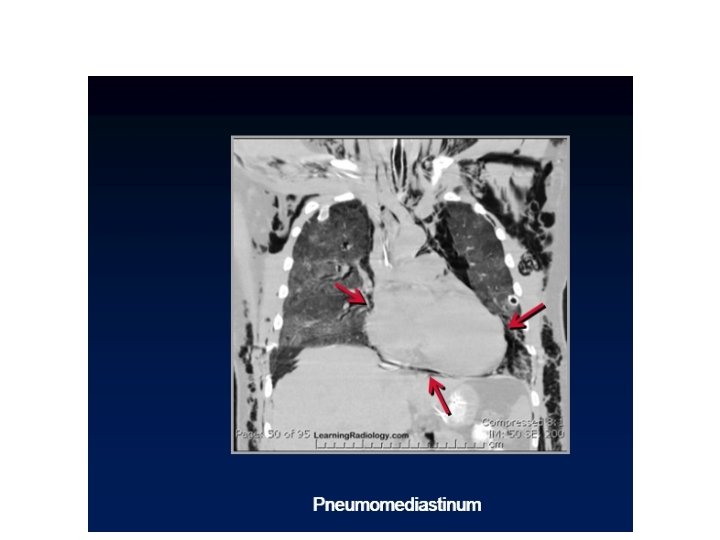

Continuous diaphragm sign